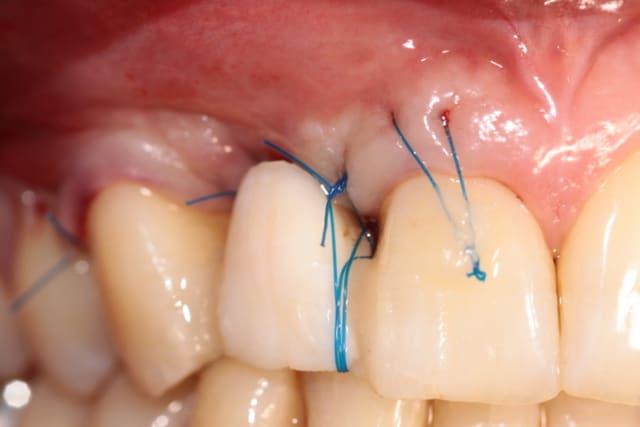

j'ai un cas similaire qui cicatrise et puisque que l'on parlait de recouvrement gingival, voilà un cas où j'espère un résultat sympa... en tout cas c'est prometteur

1 et 2 pré op

3 6 semaines après extraction

4,5,6 intervention avec pilier et barre titane

7 3 semaines post chir à la dépose des points